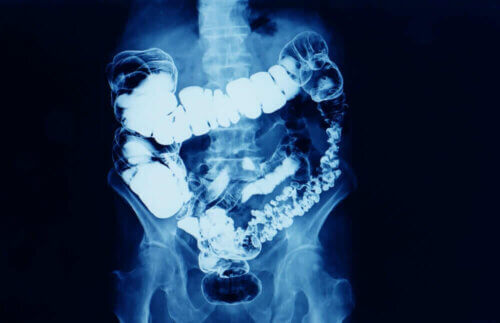

En général, on parle de constipation lorsque la fréquence des selles diminue. La constipation est un symptôme de la diminution du transit intestinal.